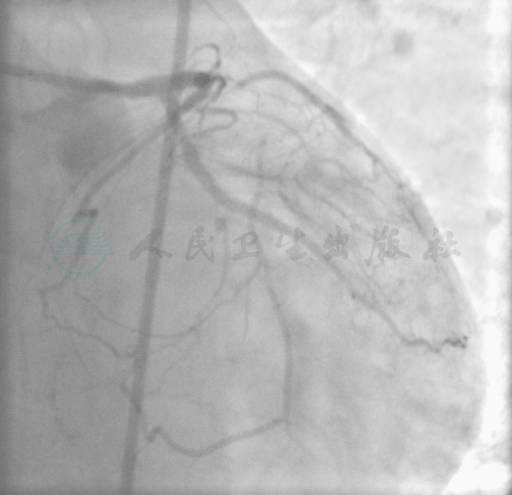

选用右桡动脉径路,6F血管鞘,常规方法行CAG。CAG示:右冠状动脉(RCA)第3段病变累及后三叉,狭窄90%(图1);左主干(LM)无狭窄;左前降支(LAD)第7段100%闭塞;第1间隔支粗大并与LAD远端的间隔支形成侧支,逆灌注使LAD远端显影(图2);左回旋支中段100%闭塞(图3)。

图2 LCX-CTO病变